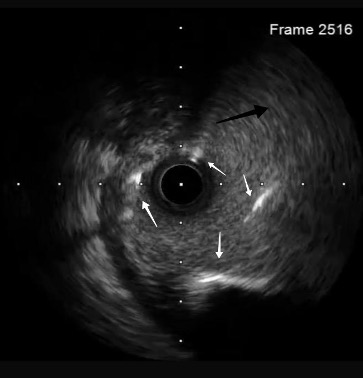

A wire was placed in the diagonal branch prophylactically to preserve side branch patency during main vessel stenting. After successful deployment of a drug-eluting stent (DES) in the LAD, the side branch wire was withdrawn. However, a radiopaque segment remained within the side branch, while the remaining wire fractured and became entrapped behind the stent struts (Figure 2 [black arrows], Video 2).

A coronary snare was used to retrieve the proximal segment of the retained wire. Partial extraction was achieved, but tangled wire fragments remained lodged in the proximal LAD. To stabilize these remnants, an additional DES was deployed to pin the wire against the vessel wall. Although angiography initially appeared satisfactory, intravascular ultrasound (OptiCross, Boston Scientific) proved pivotal by revealing that the wire loops had coiled within the stent, extended retrogradely into the proximal LAD, and reentered the stented segment near the left main stem (LMS) (Figures 2 [red arrow], 3A-C, Video 3).